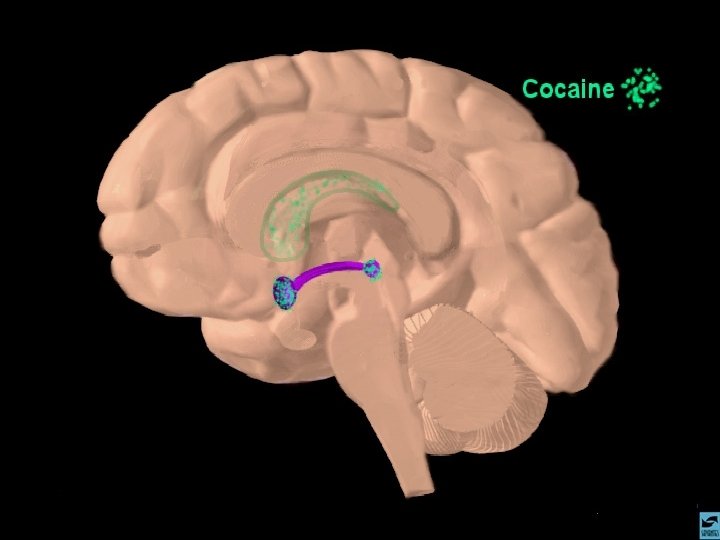

ANFETAMINAS E COCAÍNA EFEITOS CEREBRAIS: ATIVA OS SISTEMAS DOPAMINÉRGOS MESOLÍMBICOS E MESOCORTICAIS, INIBINDO A RECAPTAÇÃO DE DOPAMINA NOS TERMINAIS SINÁPTICOS E PROMOVENDO SUA LIBERAÇÃO NAS SINAPSES.